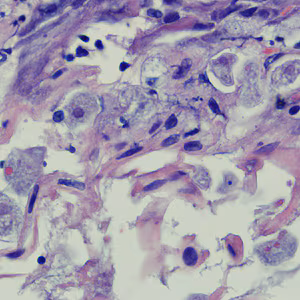

Case #258 – August, 2009

A biopsy was performed on a 23-year-old woman with no known travel history, presenting with a perianal ulcer. The specimen was preserved in formalin and sent to a pathology lab for work-up. Figures A and B show what was observed at 500x magnification from a section of the tissue, stained with hematoxylin and eosin (H&E). What is your diagnosis? Based on what criteria?

Figure A